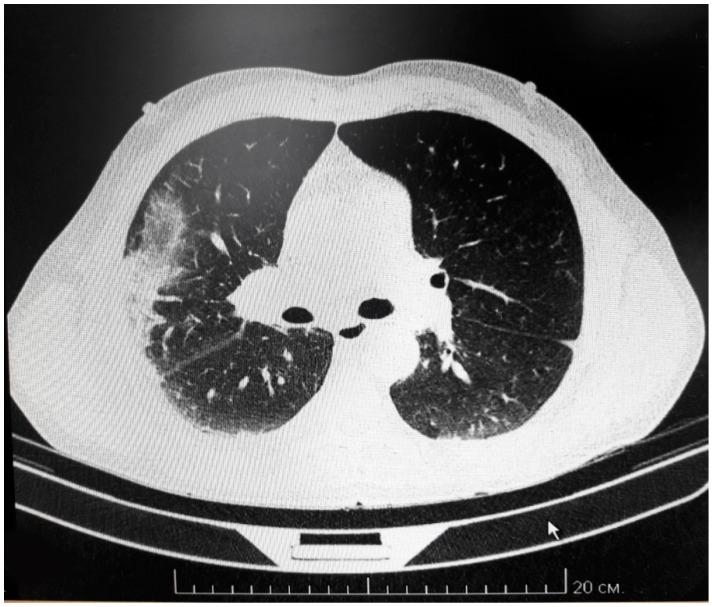

Hemorrhagic fever with renal syndrome (HFRS) is endemic in Tatarstan, where thousands of cases are registered annually. is commonly detected in human case samples as well as in captured bank voles, the rodent hosts. The pathogenesis of HFRS is still not well described, although the cytokine storm hypothesis is largely accepted. In this study, we present a comprehensive analysis of a fatal HFRS case compared with twenty four non-fatal cases where activation of the humoral and cellular immune responses, pro-inflammatory cytokines and disturbed blood coagulation were detected using immunological, histological, genetic and clinical approaches. Multiple organ failure combined with disseminated intravascular coagulation syndrome and acute renal failure was the cause of death. Decreased Interleukin (IL)-7 and increased IL-18, chemokine (C-C motif) ligand (CCL)-5, stem cell growth factor (SCGF)-b and tumor necrosis factor-beta (TNF-β) serum levels were found, supporting the cytokine storm hypothesis of hantavirus pathogenesis.

肾综合征出血热(HFRS)在鞑靼斯坦流行,每年都有数千例病例登记。该病毒在人类病例样本以及被捕的田鼠等啮齿动物宿主中均有发现。HFRS 的发病机制尚未得到很好的描述,尽管细胞因子风暴假说已被广泛接受。在这项研究中,我们对一例致命性 HFRS 病例与 24 例非致命性病例进行了综合分析,通过免疫、组织学、遗传学和临床方法检测到体液和细胞免疫反应、促炎细胞因子和凝血紊乱的激活。多器官衰竭、弥散性血管内凝血综合征和急性肾功能衰竭是死亡的原因。发现白细胞介素(IL)-7 降低和 IL-18、趋化因子(C-C 基序)配体(CCL)-5、干细胞生长因子(SCGF)-b 和肿瘤坏死因子-β(TNF-β)血清水平升高,支持汉坦病毒发病机制的细胞因子风暴假说。